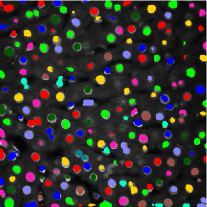

Figure 3 shows the synthetic images generated by our proposed method. The left column indicates original images whereas middle column shows synthetic images artificially generated from corresponding synthetic binary images provided in right column. As can be seen from Figure 3, the synthetic images reflect characteristics of the original microscopy images such as background noise, nuclei shape, orientation and intensity.